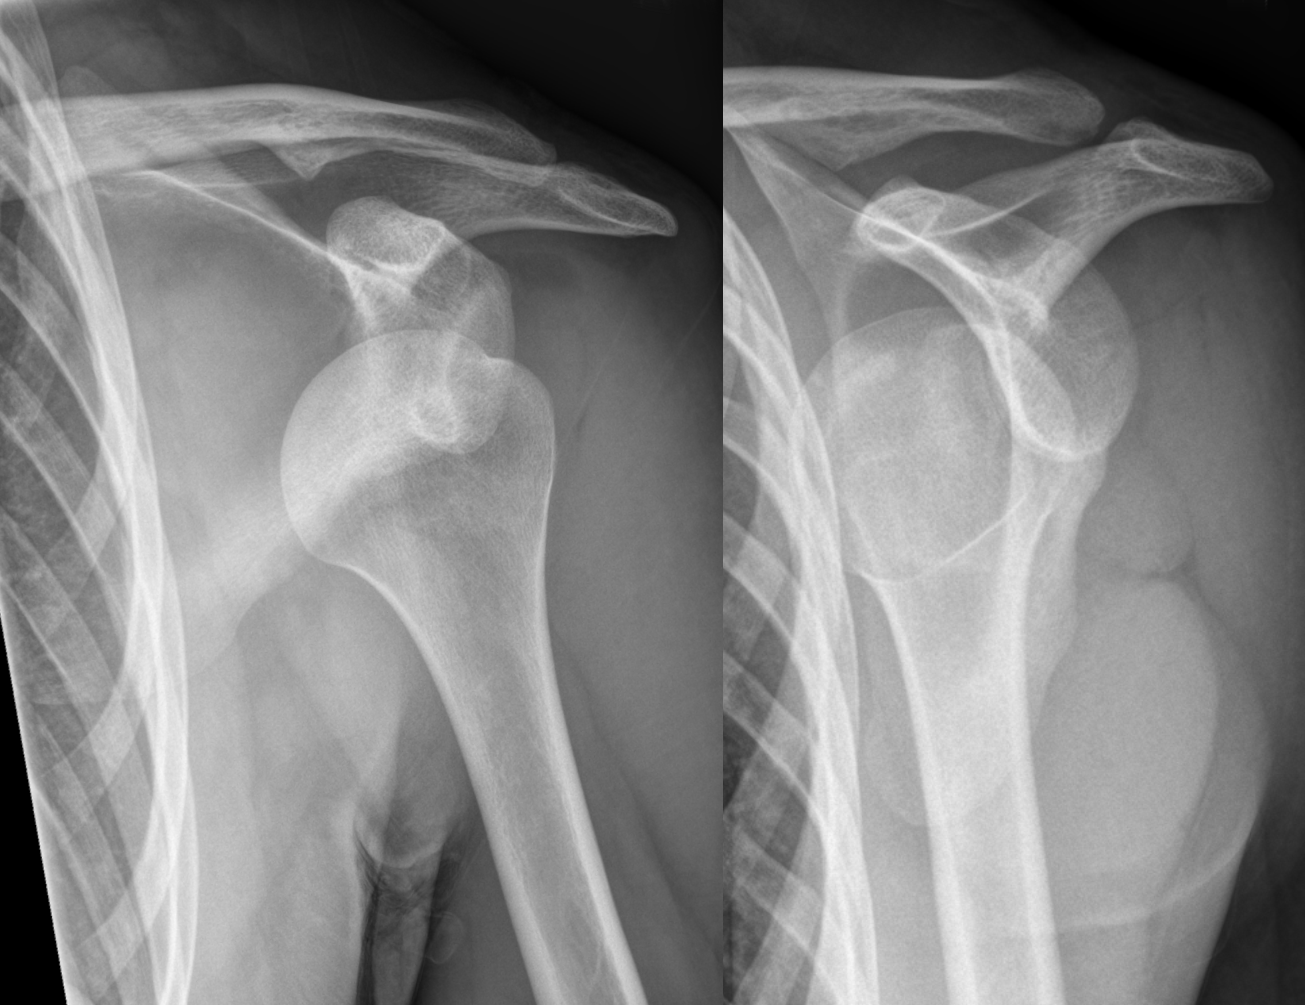

Hellerhoff - Own work, CC BY-SA 3.0, Link

Majorité des cas : luxation antérieure.

Radio de l’épaule (F + profil de Lamy)